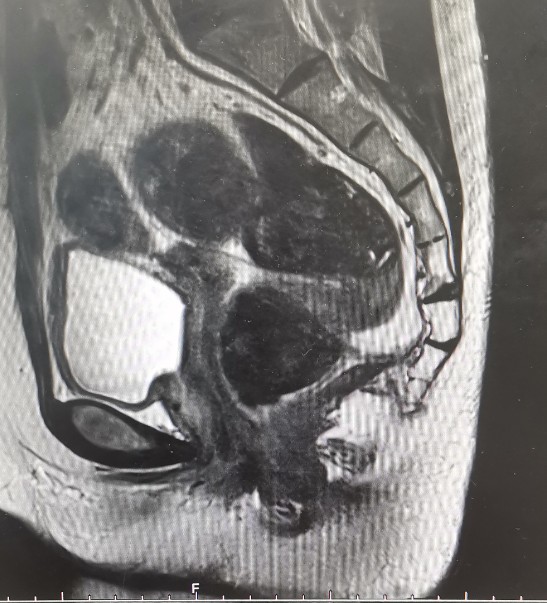

•全腹核磁:子宫术后改变,脂肪肝,双肾囊肿,盆腔少量积液。

矢状位T1

矢状位T2